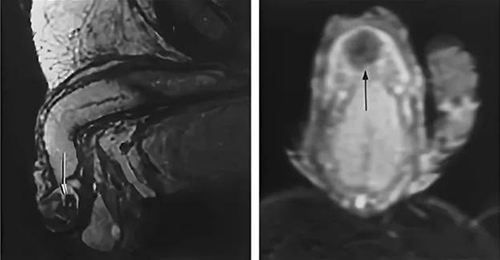

陰莖99%由海綿體組成,類似於普通的海綿。勃起時,陰莖會充滿血液並增大。陰莖由兩條主要血管供血 - 背動脈和背靜脈。血液通過動脈進入陰莖,並通過靜脈排出。事實上,勃起就是對這些血管的操縱。

你看,當男人看到一個美麗的女孩時,大腦就會發出信號,打開背動脈中的特殊瓣膜,關閉背靜脈中的相同瓣膜。射精後(或性欲消退時),情況正好相反——動脈瓣膜關閉,靜脈瓣膜打開。血液從陰莖流出,陰莖縮小。

當血管變弱時(大量男性都有這種情況),血管瓣膜的張力會下降。靜脈瓣膜尤其受到影響,因為它們維持陰莖的血壓。它們開始變弱。如果靜脈瓣膜固定"不好",男性就會勃起緩慢。如果根本沒有固定,通常就會產生陽痿。